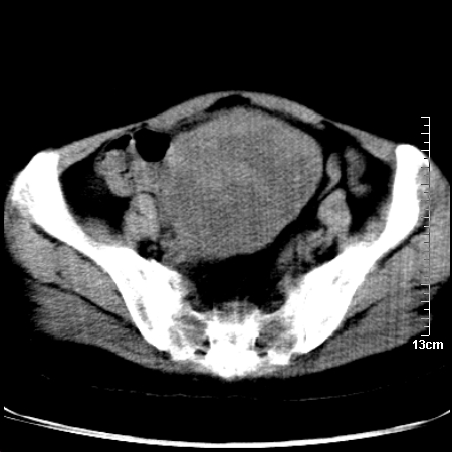

术前的疏忽,手术前诊断阑尾炎,但是没有常规做b超,导致术后1周检查发现 1。实性包块?2。腹腔术后脓肿?

病史:病人一周前诊断阑尾炎,未做b超,手术发现阑尾化脓,(没有留意有无包块),术后1周病人发热,血象:1.6万,做b超发现,随ct检查,上传图片

巨大囊实性包块,边界大部尚清楚,不太像脓肿的表现。应该做个增强检查除外盆腔肿瘤。

脓肿可能性大. 因回盲部区域化脓性兰尾切除残端感染改变征像与实性肿块关系密切.肿块上界至右下腹,下界至盆腔膀胱上缘, 如果是实性肿块在兰尾术中可能就会发现. 所以术后一周病人高烧, 白细胞增高,临床表现支持脓肿.

盆腔一边界大部份清晰囊实性肿块,其周腹脂未见确切异常,其一端与右侧附件相连。考虑右侧附件肿瘤。

如果能进行肠道准备就好了!盆腔内巨大囊实性包块,右前缘与周围肠管分界不清,病灶内前部的气体是否为肠管内气体形成的假象不能确定。

这么大一包快手术当中没有发现?值得怀疑!结合化脓性阑尾炎病史,首先考虑脓肿!不排外附件来源的肿瘤,建议增强扫描!!